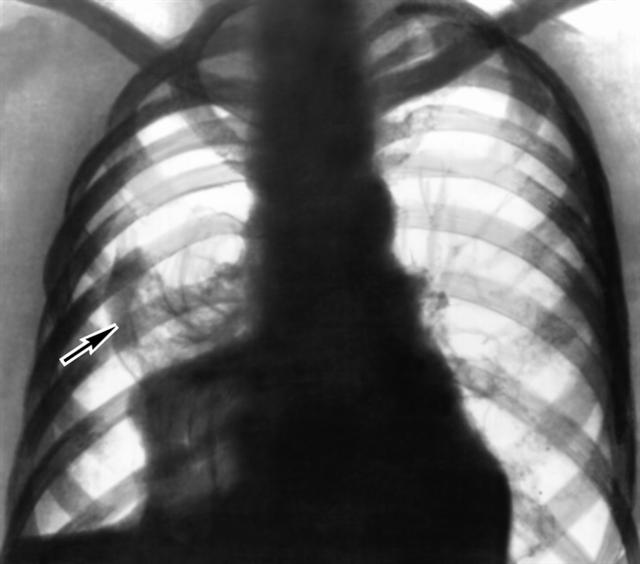

Рис. 3. Рентгенограмма органов грудной клетки при правостороннем гемопневмотораксе у больного раком легкого: правое легкое коллабировано (указано стрелкой), оставшуюся часть правой половины грудной полости занимает зона просветления без легочного рисунка (скопление воздуха) и затенение с горизонтальной верхней границей (кровь). |